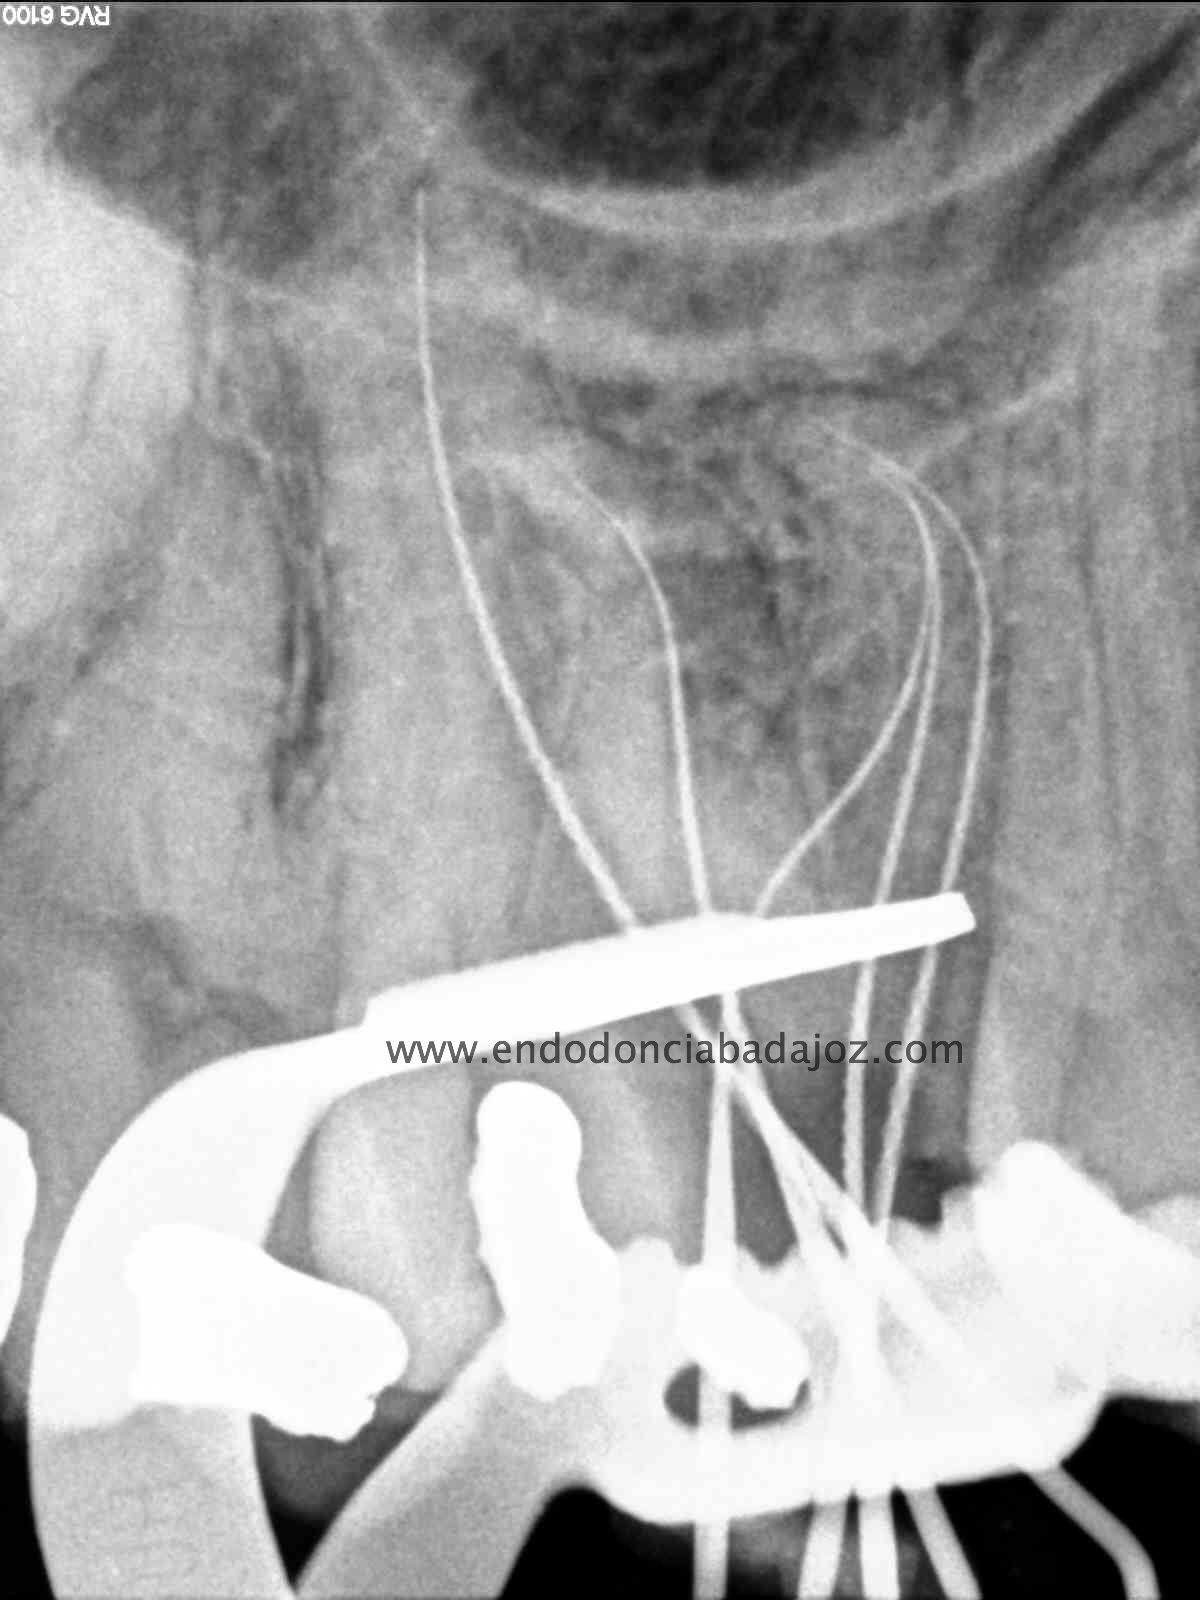

Esta última foto corresponde con un caso de un primer molar superior que la Rx no me esperaba que tuvieses tres conductos mesiales:

Son casos complicados, este en particular, por la ligera curva apical, que se agrava con la curva coronal, con lo que debemos  aliviar modificando la apertura y acceso del tercio coronal con ultrasonidos e instrumentación.

Usamos los sistemas Pathfiles y las Mtwo, consiguiendo una buena preparación  de los conductos